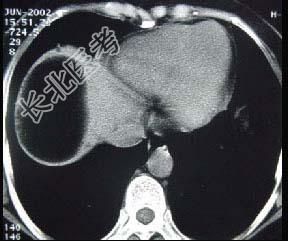

单项选择题男,30岁, 右下腹稍隆起,CT检查如图, 最可能的诊断为 ( )

A、右膈下脓肿

B、间位结肠

C、右膈下脂肪瘤

D、右下肺肺大疱

E、右下肺炎